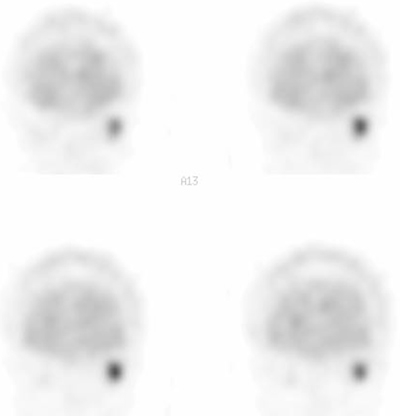

分化型甲状腺がんの多発骨転移 。

左から: 131Iシンチ, 18F-fluoride PET/CT, 18F-FDG PET/CT, 骨シンチ(プラナー像)。左腸骨、胸椎転移。